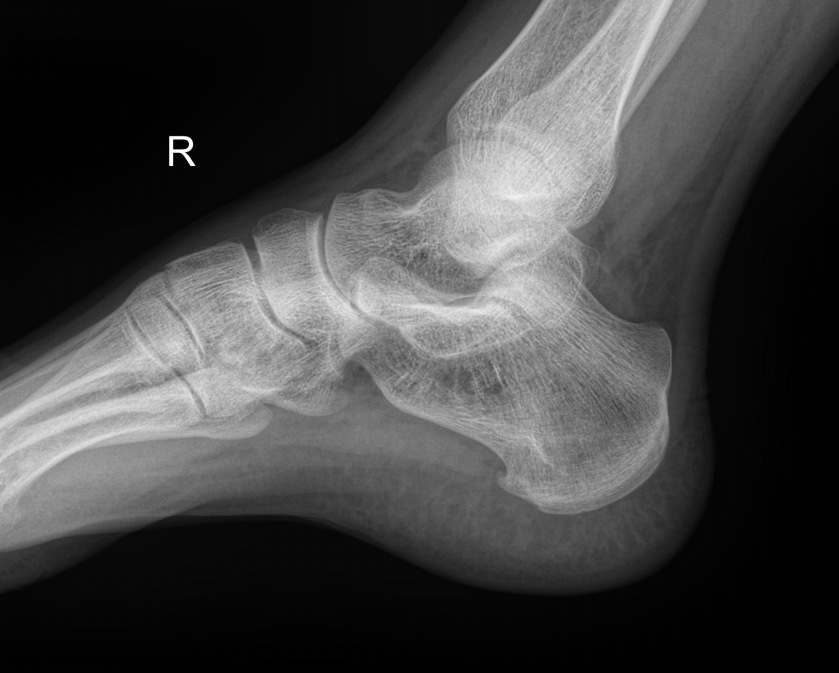

Назад Рентген пяточных костей в боковой проекции

Пяточная кость ― самая крупная среди костей стопы. Нагрузка, приходящаяся на нее, колоссальна. Отсюда и частая травматизация, связанная как со спортом, так и с бытовой и профессиональной деятельностью. Также все патологии, которые развиваются в костной ткани, могут появиться и в пяточной кости. Рентген ― наиболее часто назначаемый вид диагностики при поражении пятки.

На рентгенограмме будут отчетливо видны все структурные изменения, произошедшие с самой пяточной костью и тканями вокруг нее.

Что покажет рентген пяточных костей в боковой проекции

• Целостность кости: переломы, отломки, смещение;

• Состояние костной ткани: разрежение, склерозирование, некроз и другие изменения;

• Конгруэнтность суставных поверхностей и состояние щелей, попавших в область снимка: нормальные, измененные;

• Отечность и инородные тела в мягких тканях пятки;

• Новообразования: опухоли, остеофиты.

Стоит отметить, что остеофиты не являются причиной плантарного фасциита, а вырастают в ответ на хроническое раздражение мягких тканей и свидетельствуют о глубокой стадии заболевания.